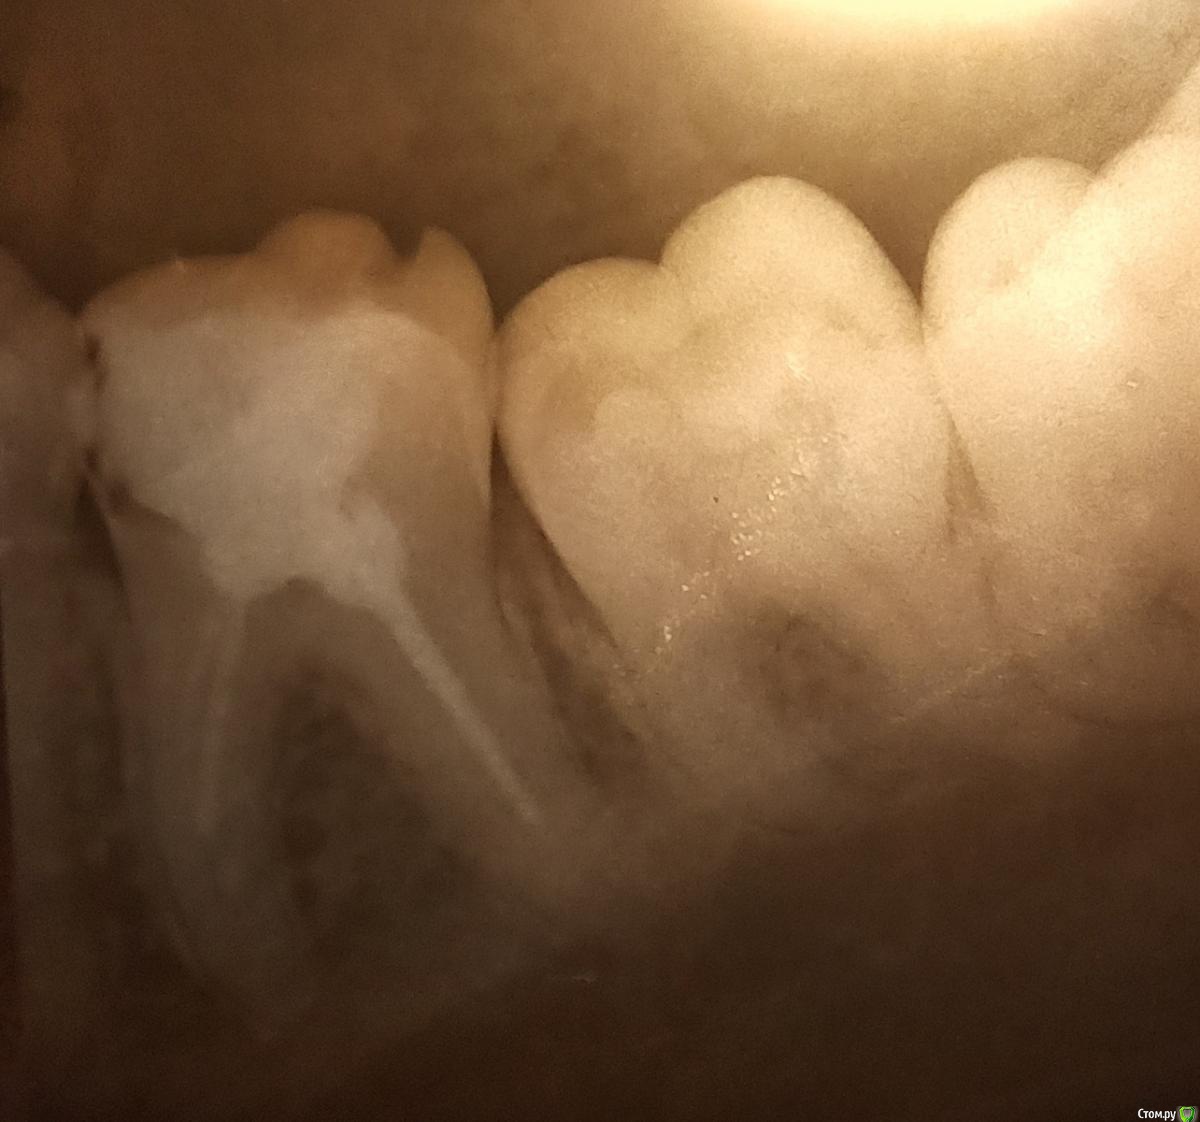

trombsky Опубликовано 5 сентября, 2020 Поделиться Опубликовано 5 сентября, 2020 (изменено) Здравствуйте. Есть снимок 36 зуба, стоит уже 15 лет цементная пломба. Возможно ли его сохранить и поставить, например, культевую вкладку, или возможно только удаление с протезированием? Зуб не болит и не беспокоит, просто терапевт посоветовала удалять цементную пломбу и, если не будет показаний к удалению, перелечивать каналы. Изменено 5 сентября, 2020 пользователем trombsky Ссылка на комментарий

trombsky Опубликовано 5 сентября, 2020 Автор Поделиться Опубликовано 5 сентября, 2020 Жалобы то какие?Жалоб нет на зуб, просто пломба стоит 15 лет, и часть оставшегося зуба крошилась, там есть небольшая дырочка. Чтобы её заделать, нужно снимать остальную пломбу, но если снять ее всю, то непонятно, в каком зуб состоянии и имеет ли смысл его лечить. Ссылка на комментарий